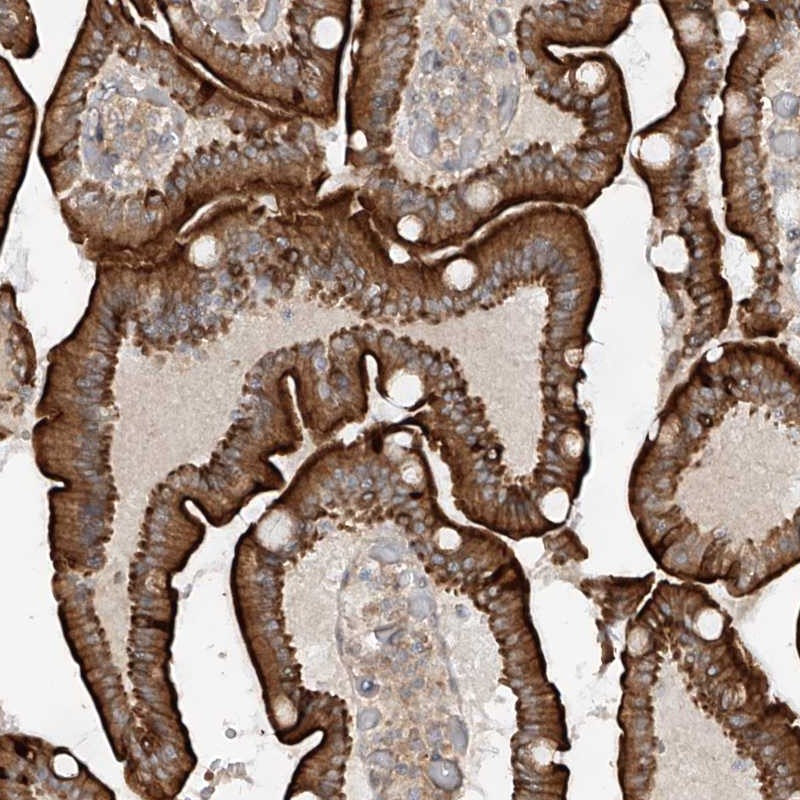

Immunohistochemical staining of human duodenum shows strong cytoplasmic positivity in glandular cells.